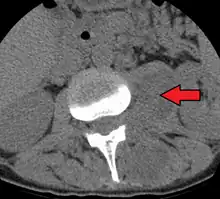

Psoas abscess is a collection of pus in the iliopsoas muscle compartment.[1][2] It can be classified into primary psoas abscess (caused by hematogenous or lymphatic spread of a pathogen) and secondary psoas abscess (resulting from contiguous spread from an adjacent infectious focus).[2]

Psoas abscess may be caused by lumbar tuberculosis. Owing to the proximal attachments of the iliopsoas, such an abscess may drain inferiorly into the upper medial thigh and present as a swelling in the region. The sheath of the muscle arises from the lumbar vertebrae and the intervertebral discs between the vertebrae. The disc is more susceptible to infection, from tuberculosis and Salmonella discitis. The infection can spread into the psoas muscle sheath.[3]